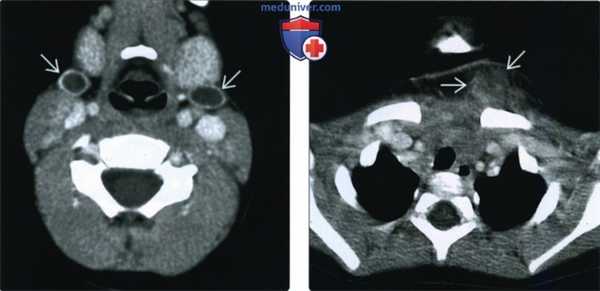

(Слева) При аксиальной КТ с КУ у пятнадцатилетнего пациента с ямкой в нижних отделах шеи спереди, замеченной после рождения, из которой появилось отделяемое (гнойная жидкость), визуализируется небольшое объемное образование с ровными краями и толстой стенкой, расположенное спереди от сонной артерии и сзади от поднижнечелюстной железы.

(Справа) При сагиттальной КТ (реконструкция) у этого же пациента определяется траектория инфицированного свищевого хода второй жаберной щели: от «ямки», меченой радиочувствительным маркером ее, до небной миндалины.

(Слева) При аксиальной КТ с КУ у ребенка в возрасте двух лет с бранхио-ото-ренальным синдромом с обеих сторон визуализируются кисты с ровными краями, не накапливающие контраст, расположенные типично (второй тип кист второй жаберной щели согласно классификации Бейли).

(Справа) При аксиальной КТ с КУ, выполненной младенцу с инфицированным синусным трактом 2-го жаберного аппарата, над ключицей визуализируется флегмонозное объемное образование воспалительного характера, лежащее под углублением в коже. Эта наиболее каудальная локализация типична для свищевого хода или фистулы.